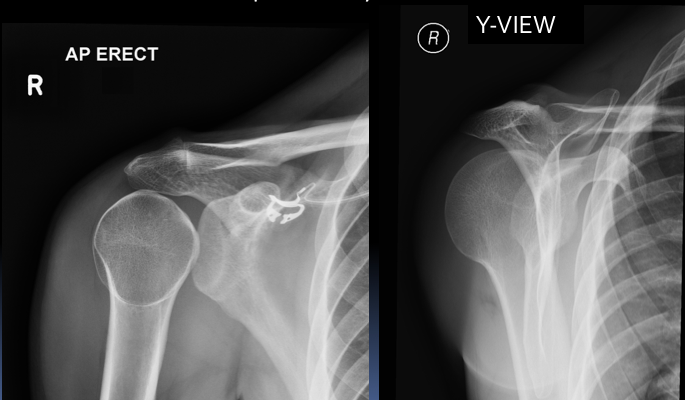

X-ray for: A 20 year old man fell whilst playing football. He had pain and deformity of his right shoulder. He cannot move it.

Does the X-ray confirm your diagnosis? What can you see in the X-rays?

AP view:

Need a 2nd view to confirm: Y-view

What are the 2 blue labels?

Coracoid process and head of humerus (seen here in anterior shoulder dislocation)

What is an AP view?

Anteroposterior view - the x-ray beam enters through the anterior aspect and exits through the posterior aspect of the chest.

What is a Y-view?

The Y-view is taken by aligning the x-ray beams parallel to the plane of the scapula so that it can be seen “floating” over the thoracic wall. In a healthy patient, the humeral head should be in alignment with the glenoid cavity of the scapula.